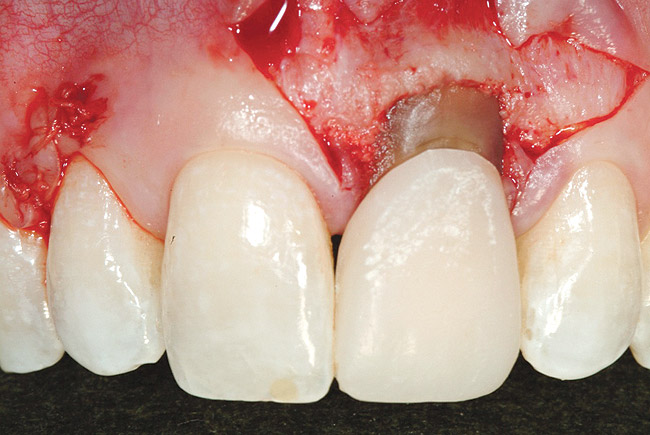

Following the surgical technique previously referenced26 with some modifications, intrasulcular incisions were made around each tooth to be treated to a minimum of one tooth on each side of the affected teeth. The incision was not carried through the entire papillae apical to the contact point, roughly being contained between the mesial and distal line angle of each affected tooth. After the incisions were made, instruments to create a tunnel under each of the incised portions of the papillae were utilized to elevate the base of the papillae. The pouch was then created by blunt dissection using a mucoperiosteal elevator extending the reflection apically past the muco­gingival junction, and laterally to the facial aspect of the tunneled papillae. Occasionally, the papillae may separate in this process, as was the situation in this case. Deepening and mobilization of the pouch was then accomplished by sharp supraperiosteal dissection, which would allow for the pouch to be coronally advanced and cover the dermal tissue completely.

Figure 7  Case One Acellular dermal matrix placed into a

Figure 7

Figure 8  Case One Acellular dermal matrix secured.

Figure 8

Figure 9  Case One Pouch coronally advanced and dermal matrix covered.

Figure 9